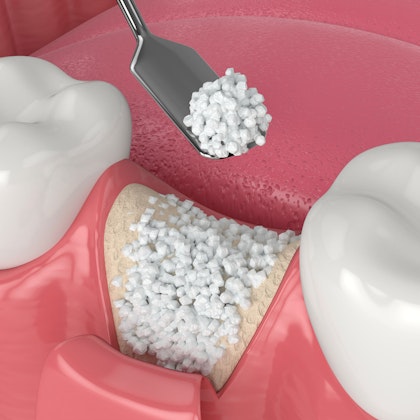

Why Are Implant-Supported Dentures So Secure? Learn About the Osseointegration Process

Did you know that losing teeth directly affects your facial structure? It leads to jawbone recession, which can cause a sunken appearance. With implants, this process is completely preventable. Implants even stimulate your jawbone and encourage bone replenishment.

Preserving Your Oral Health

Our Stockbridge, GA, team is dedicated to finding a solution that's best for your oral health. Implants encourage improved bone health and gum health. They also can help your overall health by allowing you to enjoy a more diverse diet.